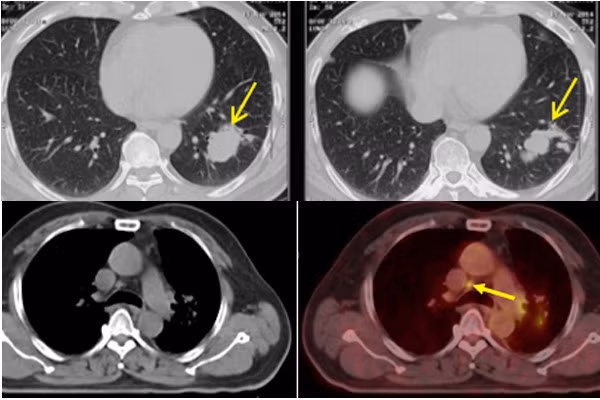

Mọi thứ vẫn diễn biến tốt cho đến năm thứ 4 (2018), khi kiểm tra PET/CT để đánh giá tổng quát, bác sĩ lại phát hiện phổi trái tái phát khối u, kích thước 4,6x1,9 cm, lan sang phổi phải và di căn lên hạch thượng đòn, hạch trước. Bệnh nhân tiếp tục được điều trị duy trì bằng hoá chất dạng uống.

Hình ảnh khối u ở phổi bệnh nhân V. (2 ảnh trên) và hình ảnh khối u thu nhỏ sau điều trị.